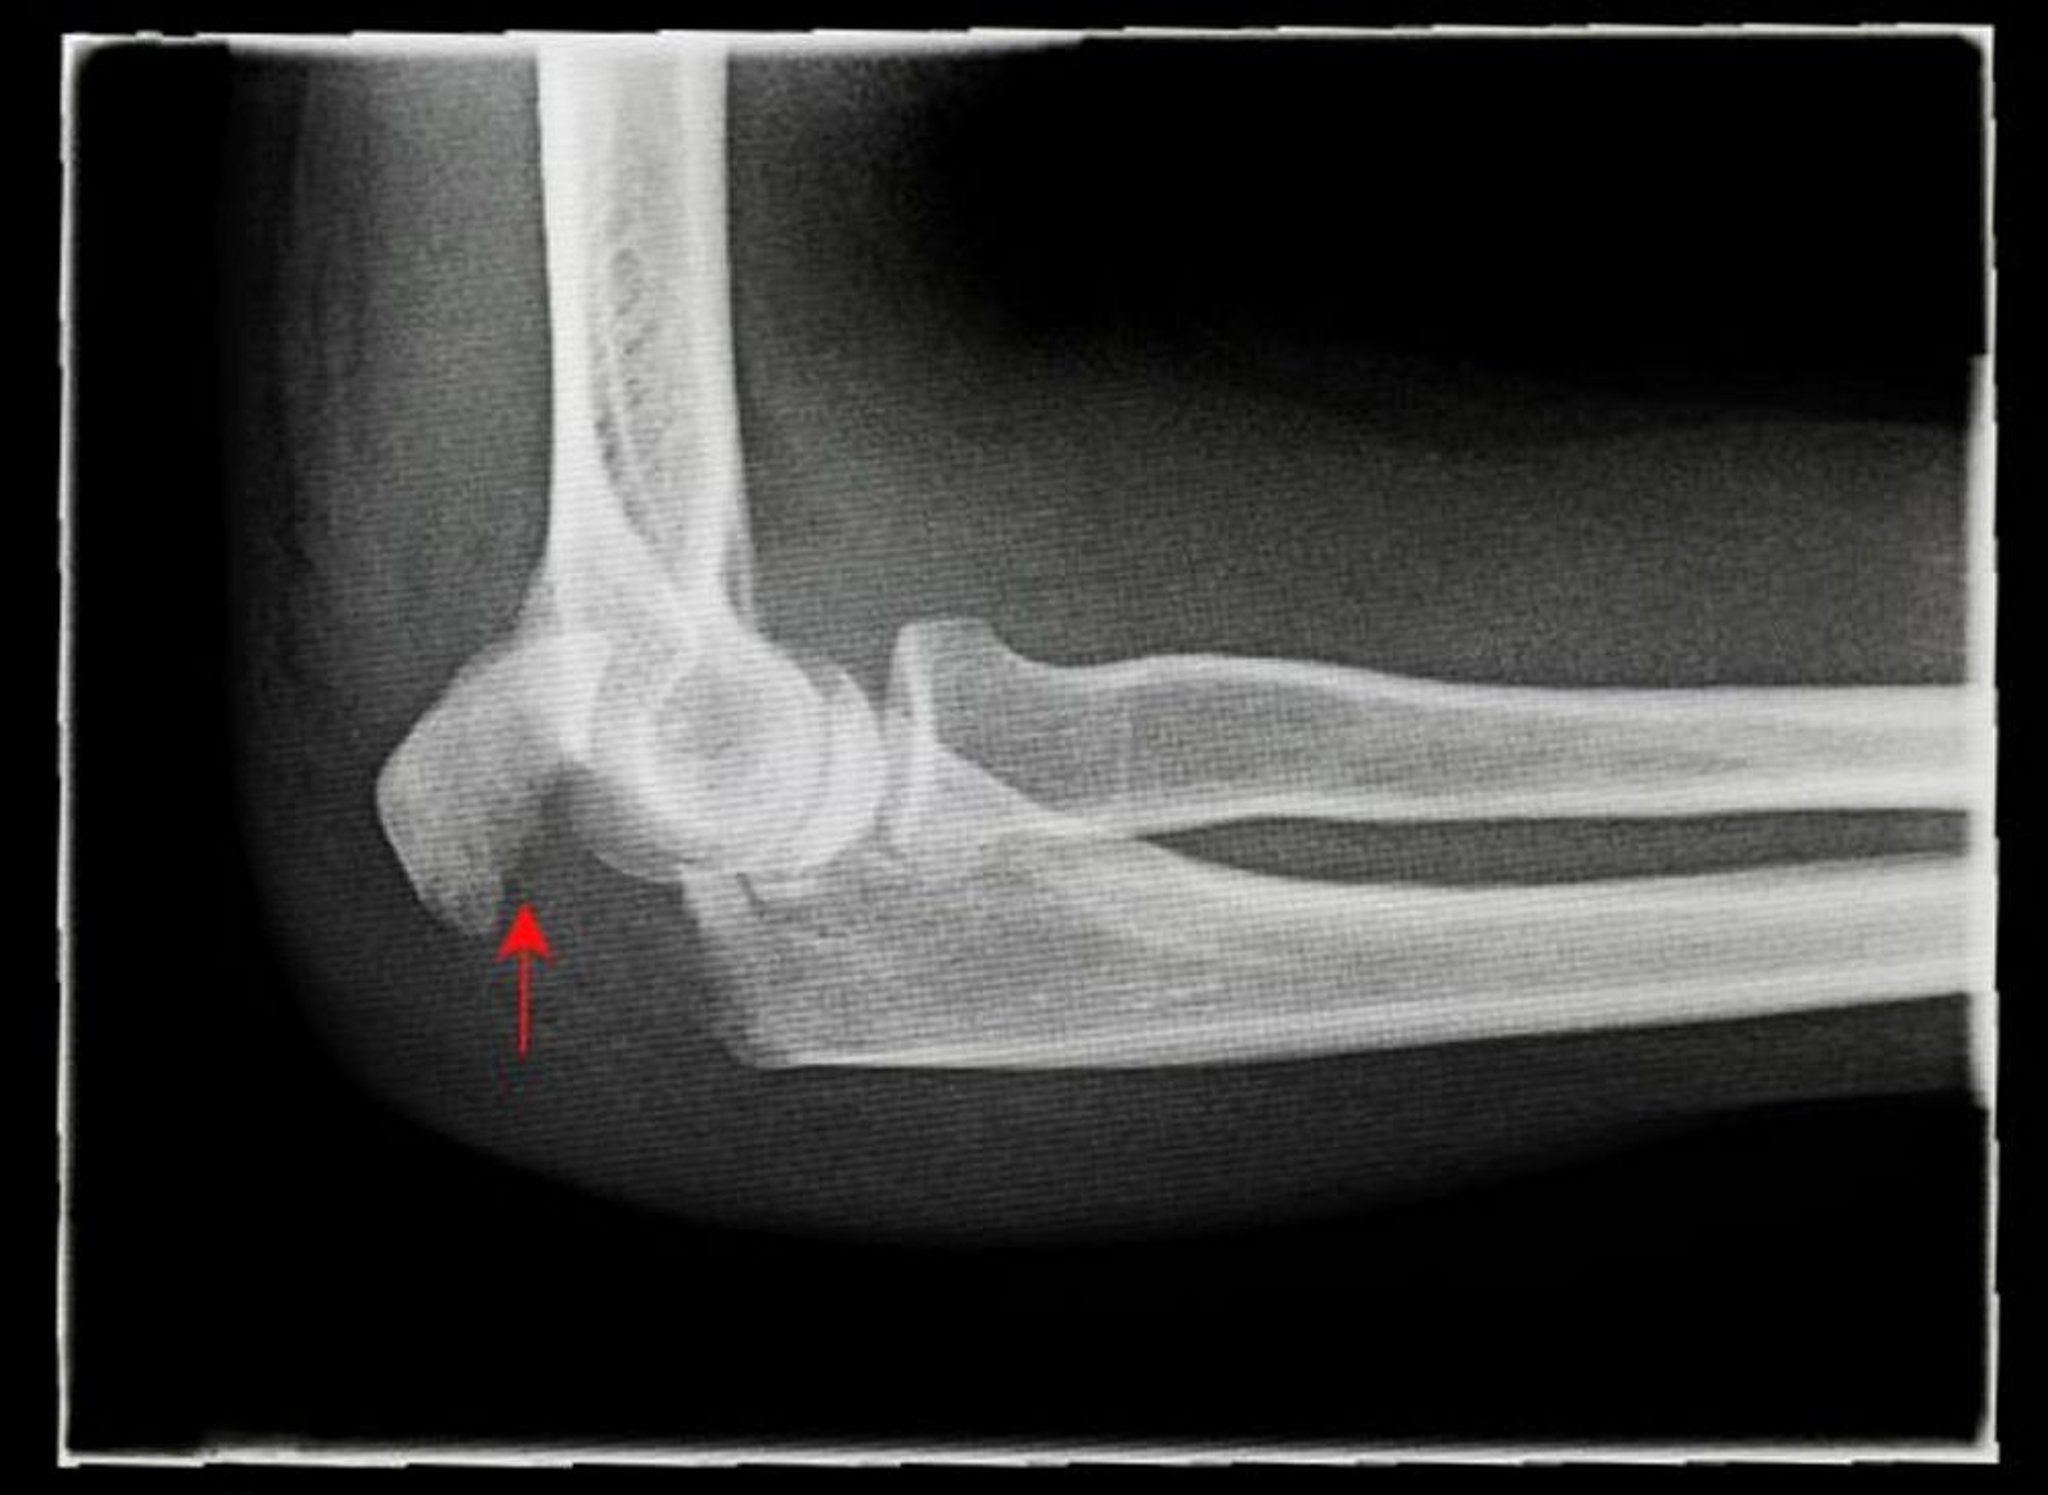

Verschobene Olekranon-Fraktur

Auf dieser Röntgenaufnahme ist eine seitliche (laterale) Ansicht einer verschobenen Olekranonfraktur (Pfeil) zu sehen.

ANTONIA REEVE/SCIENCE PHOTO LIBRARY